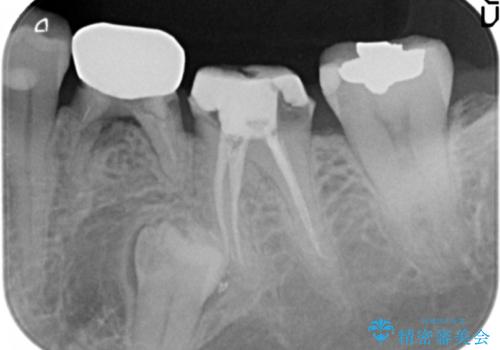

- 大人になってからも残っていた乳歯が揺れ始め、抜歯を覚悟しインプラント治療を希望して来院されました。

X線写真より、乳歯は抜歯が必要な状態でインプラントは小臼歯の埋伏により難しい状況であったのでブリッジによる補綴を選択しました。

ブリッジ治療の予知性を高めるために、虫歯の徹底的な除去に加え縁上歯質を確保するための歯周外科手術、マイクロスコープを用いた精密根管治療を行う治療計画としました。